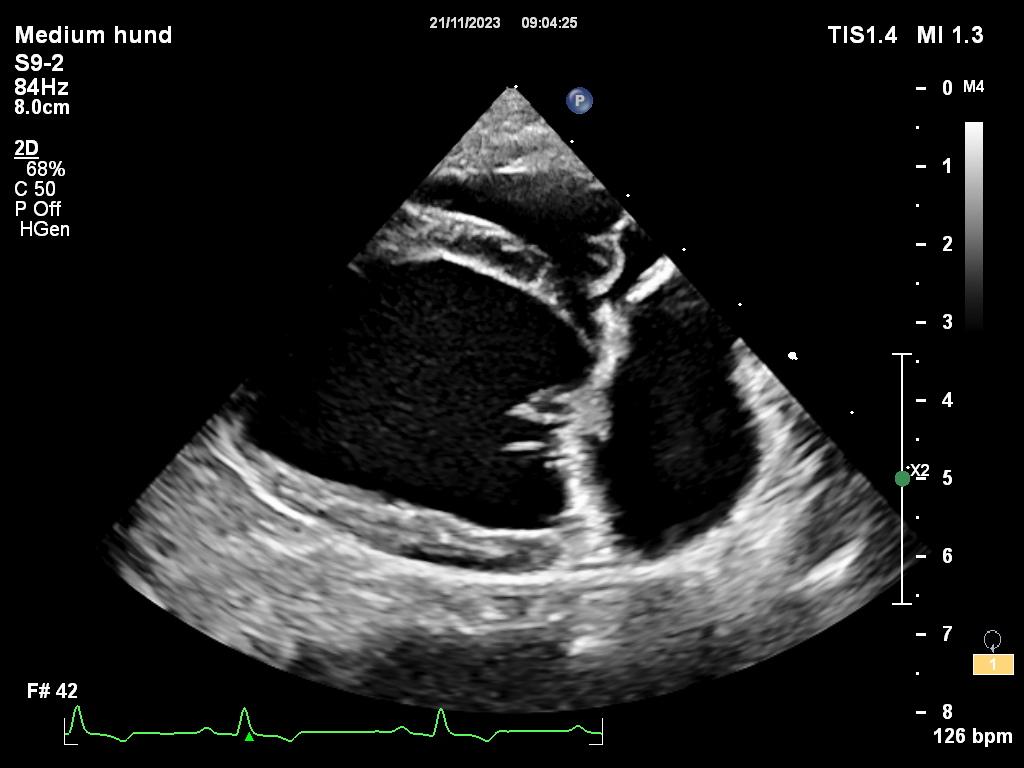

Sykdommen er genetisk betinget, oppstår i voksen alder og er oftest sett hos raser som Cavalier King Charles Spaniel, dachs og chihuahua. Klaffesykdom påvises oftest på mitralklaffen, som er klaffen som sitter mellom venstre forkammer og venstre hovedkammer. Hos hunder med MMVD vil mitralklaffen fortykkes slik at den ikke lukker seg helt igjen når blodet skal pumpes ut fra hovedkammeret gjennom aorta (hovedpulsåren). Dette fører til at noe av blodet strømmer tilbake til forkammeret og med tiden vil de venstre hjertekamrene forstørres. Disse hundene har en tydelig bilyd på hjertet og det anbefales en ultralydundersøkelse av hjertet for å avgjøre alvorlighetsgraden av sykdommen.

En ultralydundersøkelse av hjertet forteller om hunden din har utviklet forstørret forkammer og hovedkammer som følge av klaffesykdom. De hundene der hjertet har endret seg på grunn av klaffesykdommen har fordel av medisinsk behandling i form av tabletter som gis to ganger daglig. Dette er medisiner som hjelper hjertekamrene å trekke seg sammen. Medisinene forhindrer rask videreutvikling av sykdommen og senker risiko for utvikling av hjertesvikt. Hunder som får hjertemedisiner skal stå på disse livet ut, og det er sjelden man ser bivirkninger av denne typen tabletter.